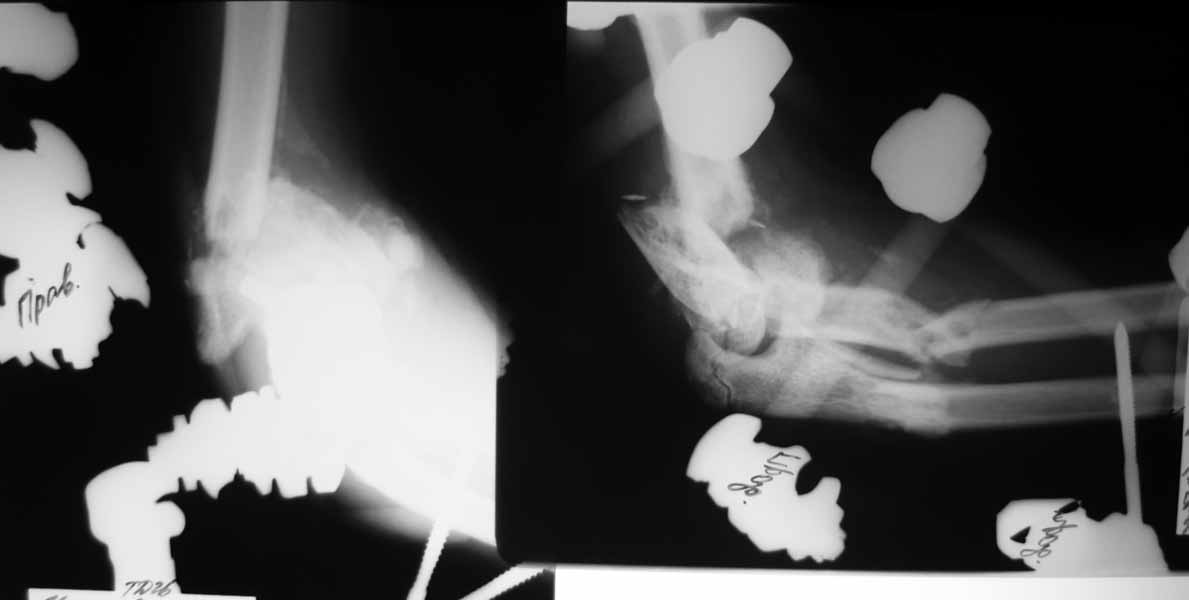

Насколько оправдано снятие аппарата? В АВФ удобнее мыть, перевязывать, не так  ли? Штанги  графитовые и больших наводок при рКТГ не дадут. Выкладываю свежие  рентгенограммы. Согласен, при таком "качестве" снимков КТ  необходимо. По поводу дистального метафиза - при благоприятном сопоставлении суставных опорных поверхностей  - дефект  заполнить  не составит большого труда.

Мысли  такие: на завтра сделаем некрэктомию участков локального сухого некроза кожи на локтевом суставе. Заживляем-первязываем. Лучевую кость  есть желание синтезировать  закрыто ESIN под ЭОП. Локтевую кость - открыто, как в пункте  4. Скорее всего - БИОС.  Пункт 4 не вызывает никаких возражений. Смущает фраза первого оперирующего: что все отломки "вбиты в мышцы как при разделке мясником и  обмотаны фасциями". При  таком взаимоотношении  с мягкими тканями сложно расчитывать на изящный выход из ситуации.